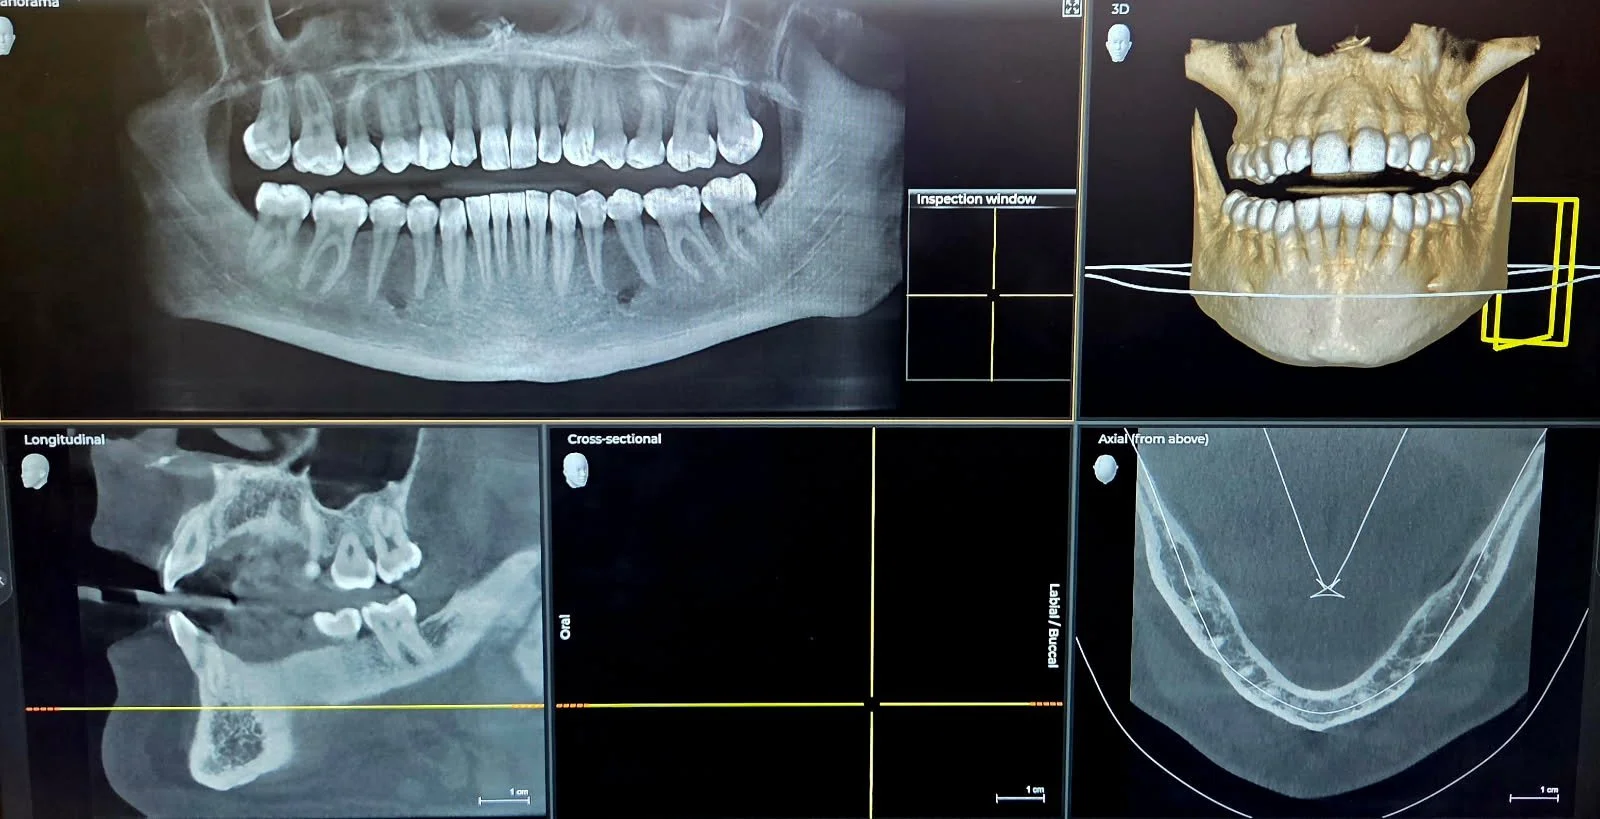

3D X-Ray

Our 3D X-ray gives Dr. Sudai a complete view of what’s going on inside the mouth, as well as bone density, and other accurate details. It picks up things traditional X-rays can miss, helping him catch issues early and plan treatment better. More insight means smarter, simpler care for you.